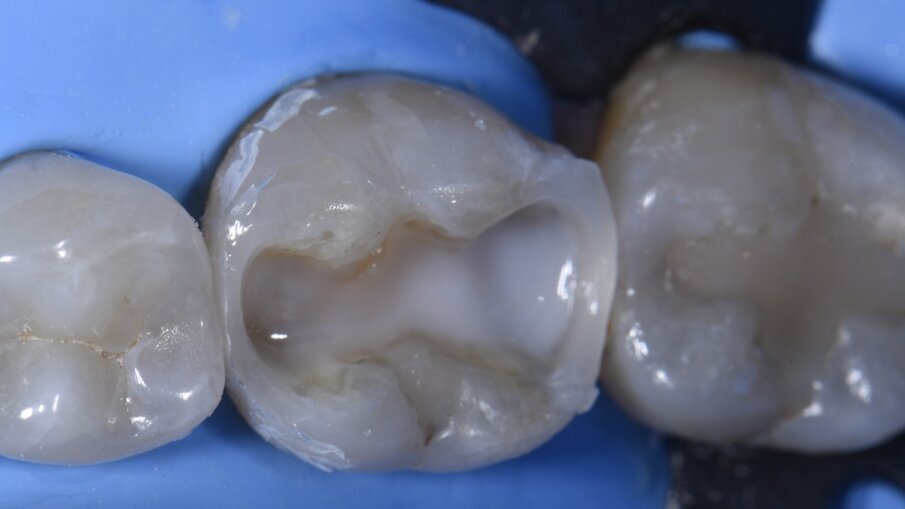

Come primo passo, si è scelto di ricostruire la parete mesiale (Fig. 3). Microstrati di un A2 fluido (Majesty esthetic, Kuraray Noritake) sono stati posizionati dopo un approccio di tipo total etch con MPa Bond (Clinicians Choice). A questo è stato permesso di disaccoppiarsi con il tempo per consentire la maturazione e l’ibridazione finale del legame alla dentina per il massimo rafforzamento del legame microtensile. La parete prossimale è stata ricostruita in strati orizzontali con incrementi di 1 mm in modo occlusale come prescritto dalla tecnica di Nikolaenko et al., consentendo valori massimi di forza di adesione microtensile. Dopo la polimerizzazione per una durata di 20 secondi, il gruppo della matrice sezionale è stato rimosso, l’anatomia del punto di contatto e la forza valutate con il filo interdentale prima dell’assemblaggio della matrice per ricostruire la parete prossimale in modo simile (Fig. 4). A seguito della costruzione della parete distale e dei relativi controlli, si è creata una situazione di Classe 1, priva di anelli di tensione e altri accessori che possono impedire l’accesso per la stratificazione occlusale (Fig. 5). La preferenza dell’autore di ricostruire una parete alla volta con matrici mesiali e distali posizionate separatamente attraverso il processo è in contrasto con i risultati della forza di contatto prossimale (PCS) di Sabre et al., che promuovono il posizionamento simultaneo di assemblaggi mesiali e distali. L’autore ritiene che il primo metodo sia più prevedibile soprattutto su denti più piccoli come i premolari, dove possono esserci difficoltà fisiche con il posizionamento simultaneo di matrici mesiali e distali a causa della necessità di sovrapporre Slick Bands insieme al rischio di comportamento a fisarmonica della matrice.

Il piano occlusale è stato anche microstratificato orizzontalmente con un composito fluido bianco opaco (tonalità Herculite Ultra Flowable XL2, KavoKerr) per bloccare la dentina scura (Fig. 5) prima del completamento della stratificazione si è usata una tonalità A2 di Voco Grandio SO. Le tinte occlusali sono state applicate utilizzando il marrone (Final Touch, Voco) (Fig. 6). Nel complesso, una sessione di restauro molto soddisfacente seguendo un protocollo graduale che riduce lo stress, aumenta la prevedibilità e consente prestazioni ottimali dei materiali e della ricostruzione estetica della struttura del dente mancante in una procedura piacevole sia per il paziente che per il medico (Fig. 7).